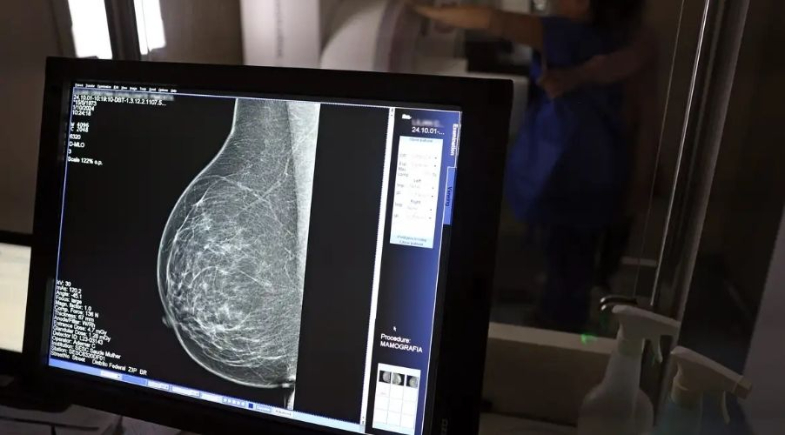

O exame clínico das mamas e a mamografia são as principais formas de detectar precocemente a doença.